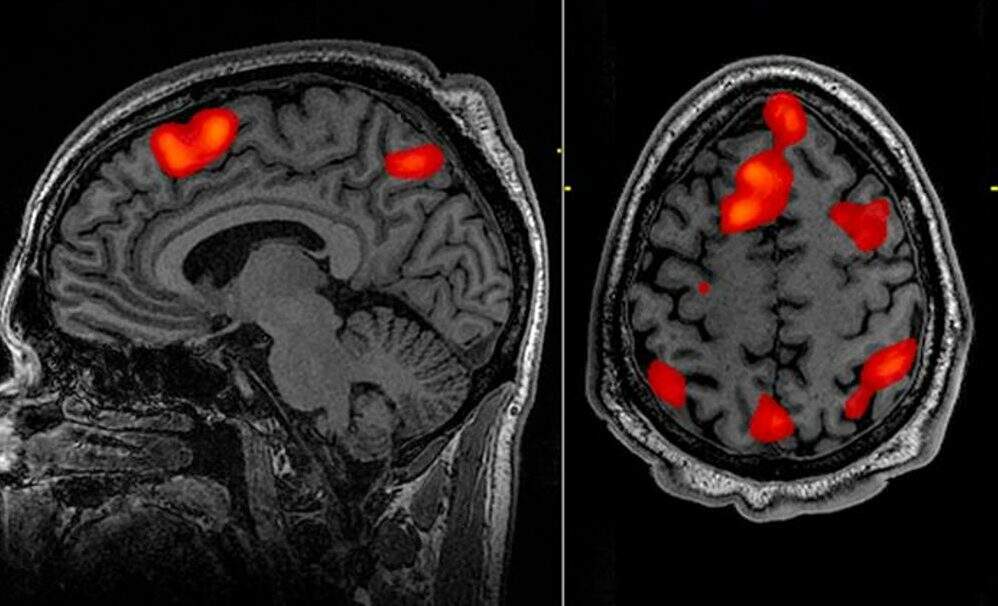

Uma pessoa no momento da morte pode estar revivendo alguns dos melhores momentos que vivenciou em sua vida. (Foto: Reprodução)

Enquanto um grupo de neurocientistas avaliava um paciente de 87 anos com epilepsia, o idoso acabou sofrendo um ataque cardíaco e morreu. Diante do resultado inesperado, foram obtidos dados inéditos de como o cérebro se comporta na hora da morte, e o que impressionou os pesquisadores foi a indicação de que lembranças da vida são resgatadas nos últimos momentos de vida. Tal percepção foi revelada por padrões de ondas rítmicas semelhantes às que são registradas durante o sono ou a meditação.

A ondas cerebrais do tipo gama mencionadas por Zemmar são referentes a funções altamente cognitivas, relacionadas à concentração, sonhos, meditação, recuperação de memória e processamento de informações. Por isso, o cientista avalia que o cérebro pode reproduzir uma última lembrança de eventos importantes da vida pouco antes da morte através da geração de tais oscilações.